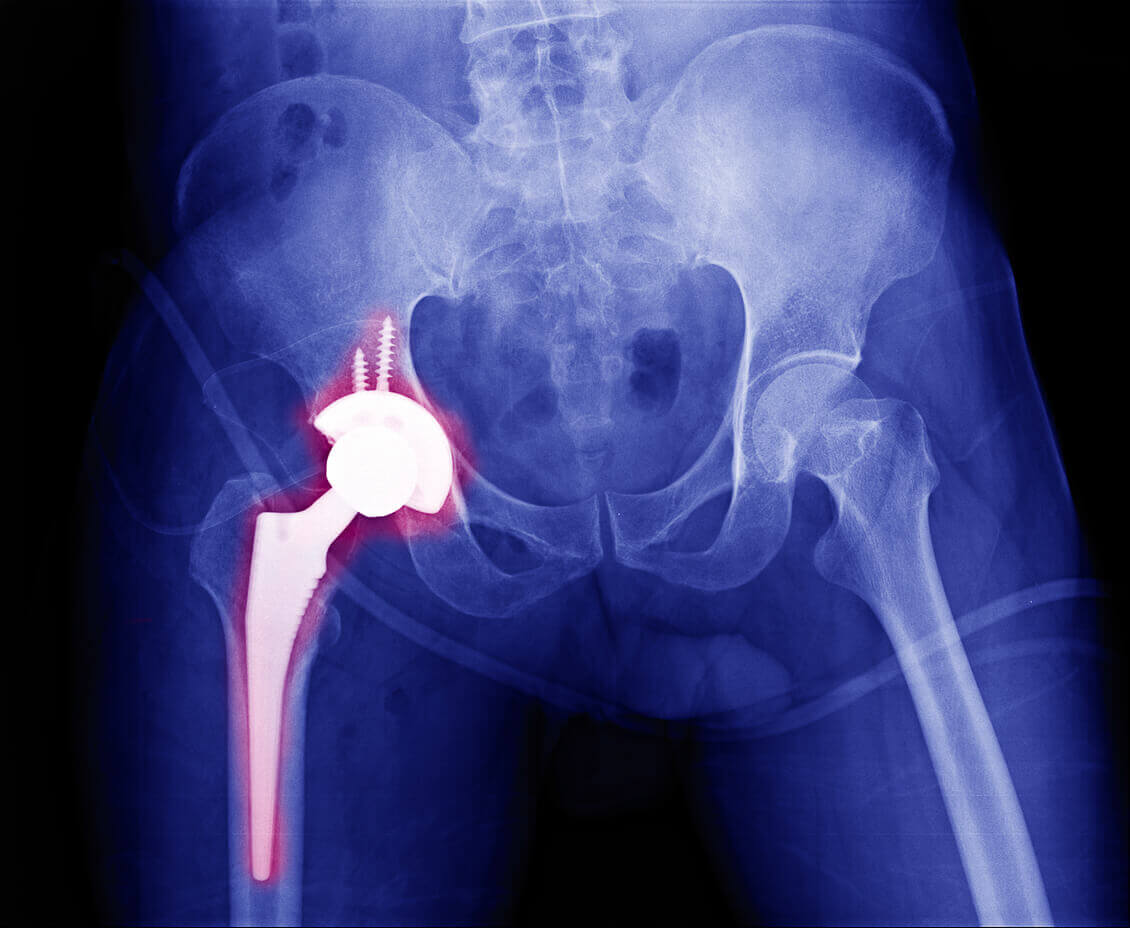

Hip Replacement

Comprehensive care for severe hip arthritis, fractures, and degenerative conditions—providing improved stability, flexibility, and pain relief.